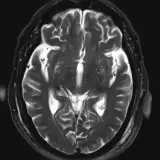

Over 2,100 interactive radiology cases, curated by radiologists for your level of training. Scroll, window, and view cases full screen — just like on PACS. Click linked findings in each writeup to jump straight to them on the image. Cases include sample reports, a focused discussion section, original illustrations, and videos.

完全交互式病例,配备您在 PACS 上期待的各项工具——滚动、调窗、缩放、平移、测量、ROI 和全屏模式。

丰富的标注直接在病例图像上突出关键发现。点击病例讲解中的关联发现,即可跳转至其在扫描上的精确位置。